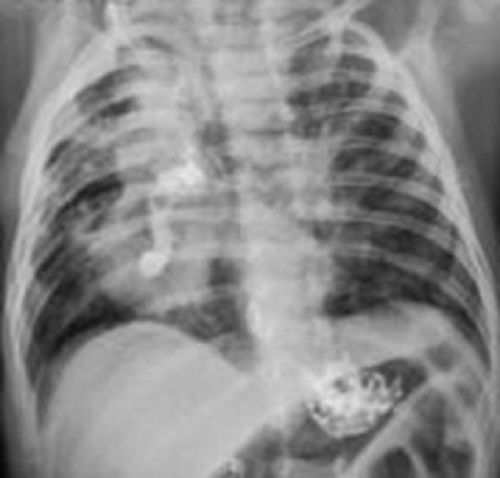

After the mandated period of the home, quarantine was over, the patient was readmitted 2 weeks later with some weight gain. A contrast study was performed with oral contrast, which demonstrated leakage from anastomosis communicating with an abscess cavity probably in the right lower lobe (Fig. 1). After stabilization, he was explored again through right posterolateral thoracotomy. On exploration, the esophagus at the anastomotic site was found to be communicating with lung parenchyma again. The leakage site from the lung parenchyma was laid open to reveal multiple bronchi opening in the lung abscess that was communicating with the esophagus (Fig. 2). Individual bronchial openings were closed, and the abscess cavity was left open. The esophageal anastomosis was performed again. The child had an uneventful recovery, with jejunostomy feeding starting the next day and oral feeding after 10 days.

Contrast study with oral Iohexol. The leak of contrast from the esophagus into a cavity in relation to the right lower lobe is evident.